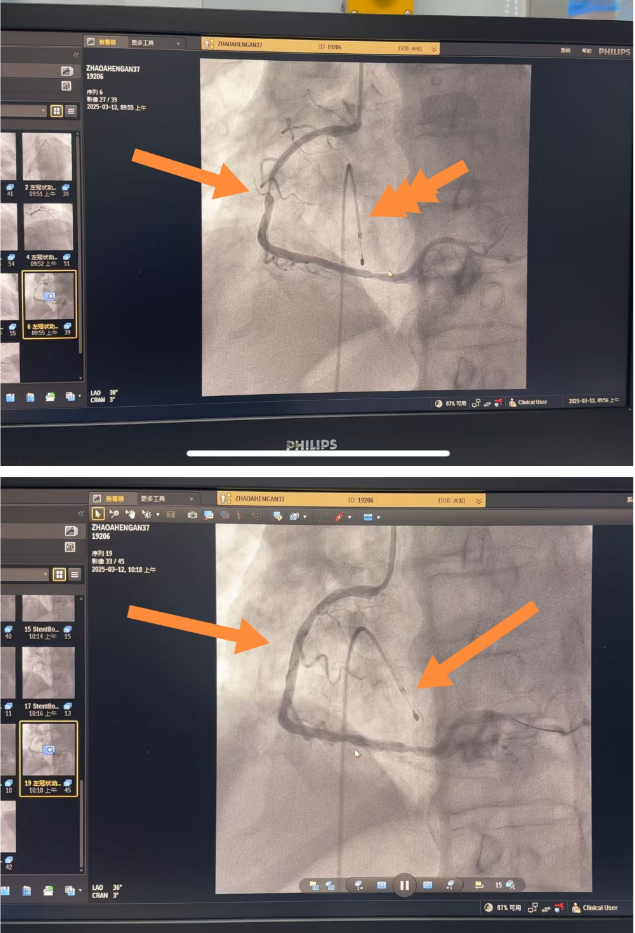

随后,经术前纠正心衰,并给予双抗治疗,以稳定病情。因患者有慢性心房纤颤,心率30次/分。为确保手术安全,由介入室主任医师葛兴利亲自领衔介入团队,为患者置入临时起搏器。临时起搏器可在手术过程中按需调整心率,保证心脏正常跳动和泵血功能,为PCI术的顺利实施保驾护航。于右侧冠状动脉近中段置入一枚支架。手术过程顺利,术后患者生命体征平稳,安返病房。